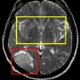

Innovative Therapien bei Schlaganfall: Interregionale Tagung in Bozen

LPA - Experten aus Tirol, Trient und Südtirol befassen sich am 28. Juni in Bozen bei der Tagung „Iktus“ mit neuesten Erkenntnissen zur Vorbeugung, Diagnose und Therapie bei Schlaganfall. Die Tagung wird vom Landesamt für Krankenhäuser in der Landesabteilung Gesundheitswesen organisiert und vom EVTZ „Europaregion Tirol-Südtirol-Trentino“ unterstützt.